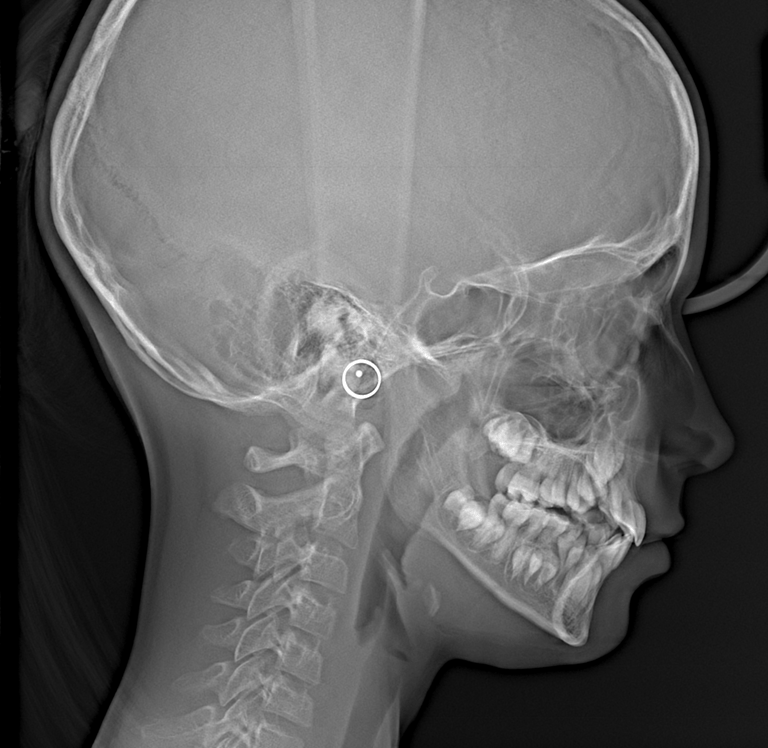

Telerentgenografia boczna (RTG cefalometryczne) – Gdynia

Telerentgenografia w projekcji bocznej, znana również jako RTG cefalometryczne, to jedno z kluczowych badań w ortodoncji i chirurgii stomatologicznej. Umożliwia dokładną analizę układu kostnego twarzoczaszki, proporcji twarzy oraz relacji zębów względem szczęki i żuchwy.

W naszej pracowni RTG stomatologicznego w Gdyni wykonujemy telerentgenogramy boczne, które są niezbędne w diagnostyce wad zgryzu, monitorowaniu postępów leczenia oraz ocenie rozwoju struktur kostnych. Badanie pozwala lekarzowi precyzyjnie zaplanować leczenie ortodontyczne i chirurgiczne, zapewniając bezpieczeństwo pacjenta i wysoką jakość obrazu.